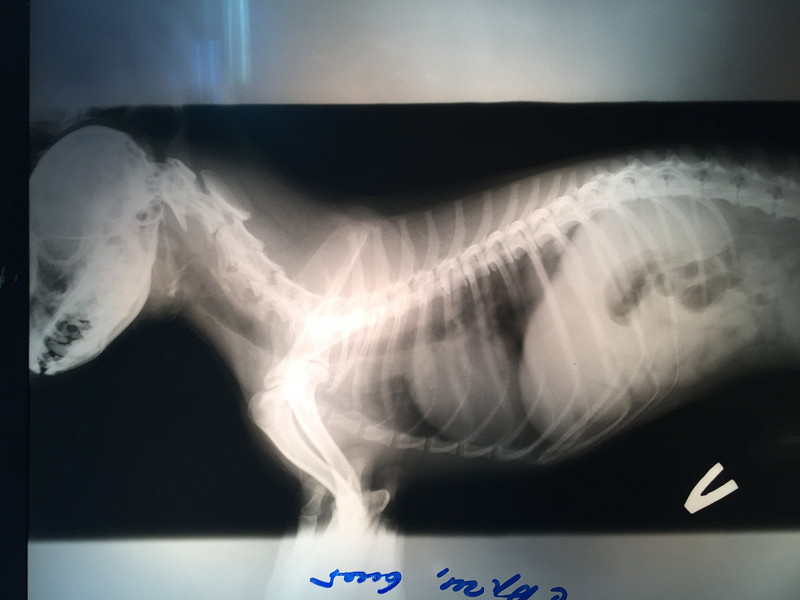

Защемление у собаки

Защемление у собаки 114 фото